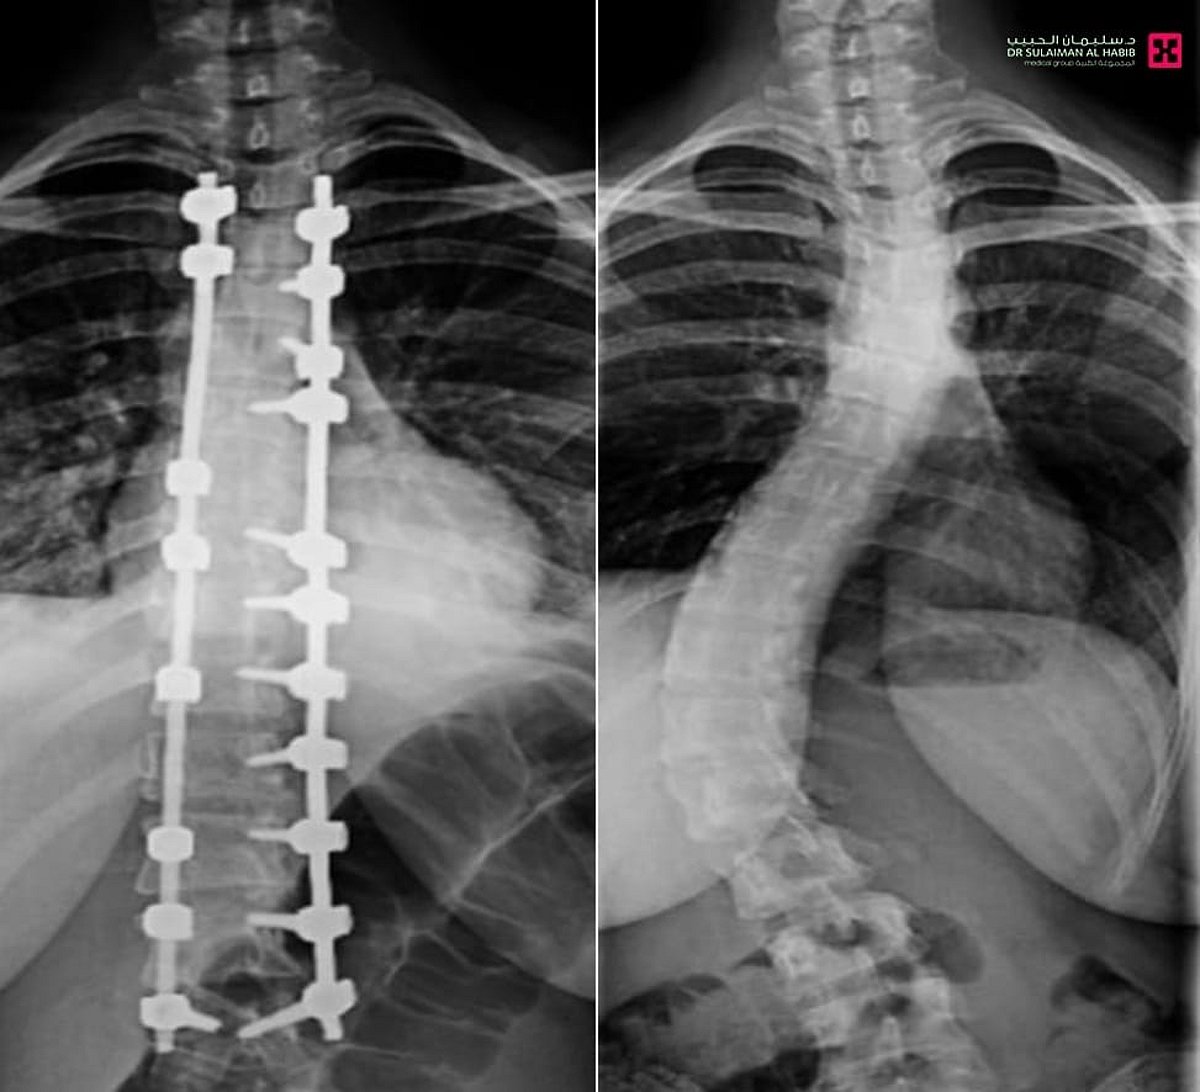

مستشفى الدكتور سليمان الحبيب بالصحافة ينجح في تصحيح ميلان حاد بالعمود الفقري لـ”عشرينية” ويعيدها للحياة الطبيعية

تمكّن فريق طبي في مستشفى الدكتور سليمان الحبيب بالصحافة، من إجراء عملية نوعية ناجحة لتقويم تشوّه متطور بالعمود الفقري لشابة عشرينية، كانت تعاني من ميلان (جنف) بدرجة “55” وتحدّب صدري بمقدار “70” درجة، ما سبّب لها صعوبات في الجلوس والمشي بشكل مستقيم، وأثّر سلبًا على حياتها الاجتماعية والنفسية، ذكر ذلك د. تركي العنزي استشاري المخ والأعصاب وجراحات العمود الفقري المعقّدة، رئيس الفريق الطبي المعالج.